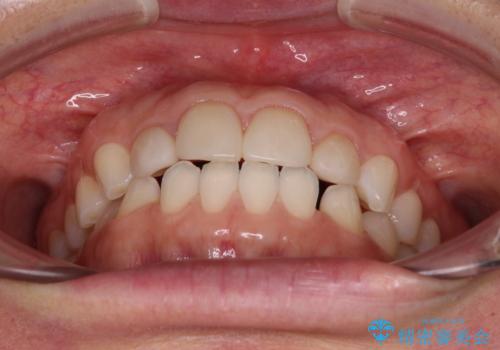

前歯を綺麗にしたい 部分矯正とセラミック治療

- 大きすぎる上顎前歯と、隙間の空いた下顎歯列を気にして来院された患者様です。

上顎前歯にはセラミッククラウンが装着されており、顔や他の歯と比較して幅の大きい状態でした。

下顎前歯は空隙歯列弓であったので、アンカースクリューとワイヤー装置を用いてスペースを閉じていくこととし、上顎前歯は矯正治療用の仮歯に置き換えた上で、仮歯の大きさを削って小さくしながら、上下前歯部の部分矯正を行うこととしました。